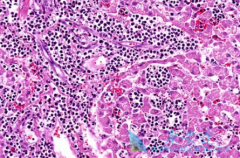

• 人们常说的血癌是白血病吗?白血病传染吗?

人们常说的血癌是白血病吗?白血病传染吗?

什么是 血癌 ?血癌就是医学上的白血病,血癌只是一种俗称,在众多恶性肿瘤中,白血病是十大高发恶性肿瘤之一。那 白血病传染吗 ?白血病是不会传染的,白血病主要是一种与血液有关的疾病,比如造血细胞出现了障碍,是造血系统的恶性肿瘤,主要与人的血液细 ...